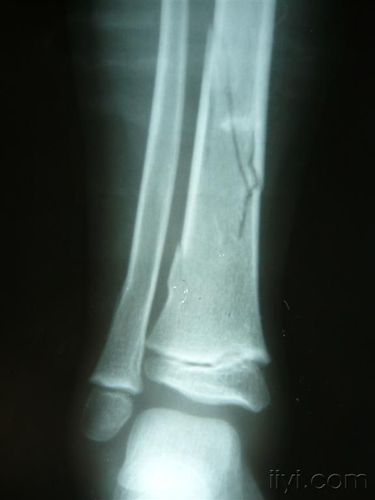

仔细看腓骨,有青枝骨折